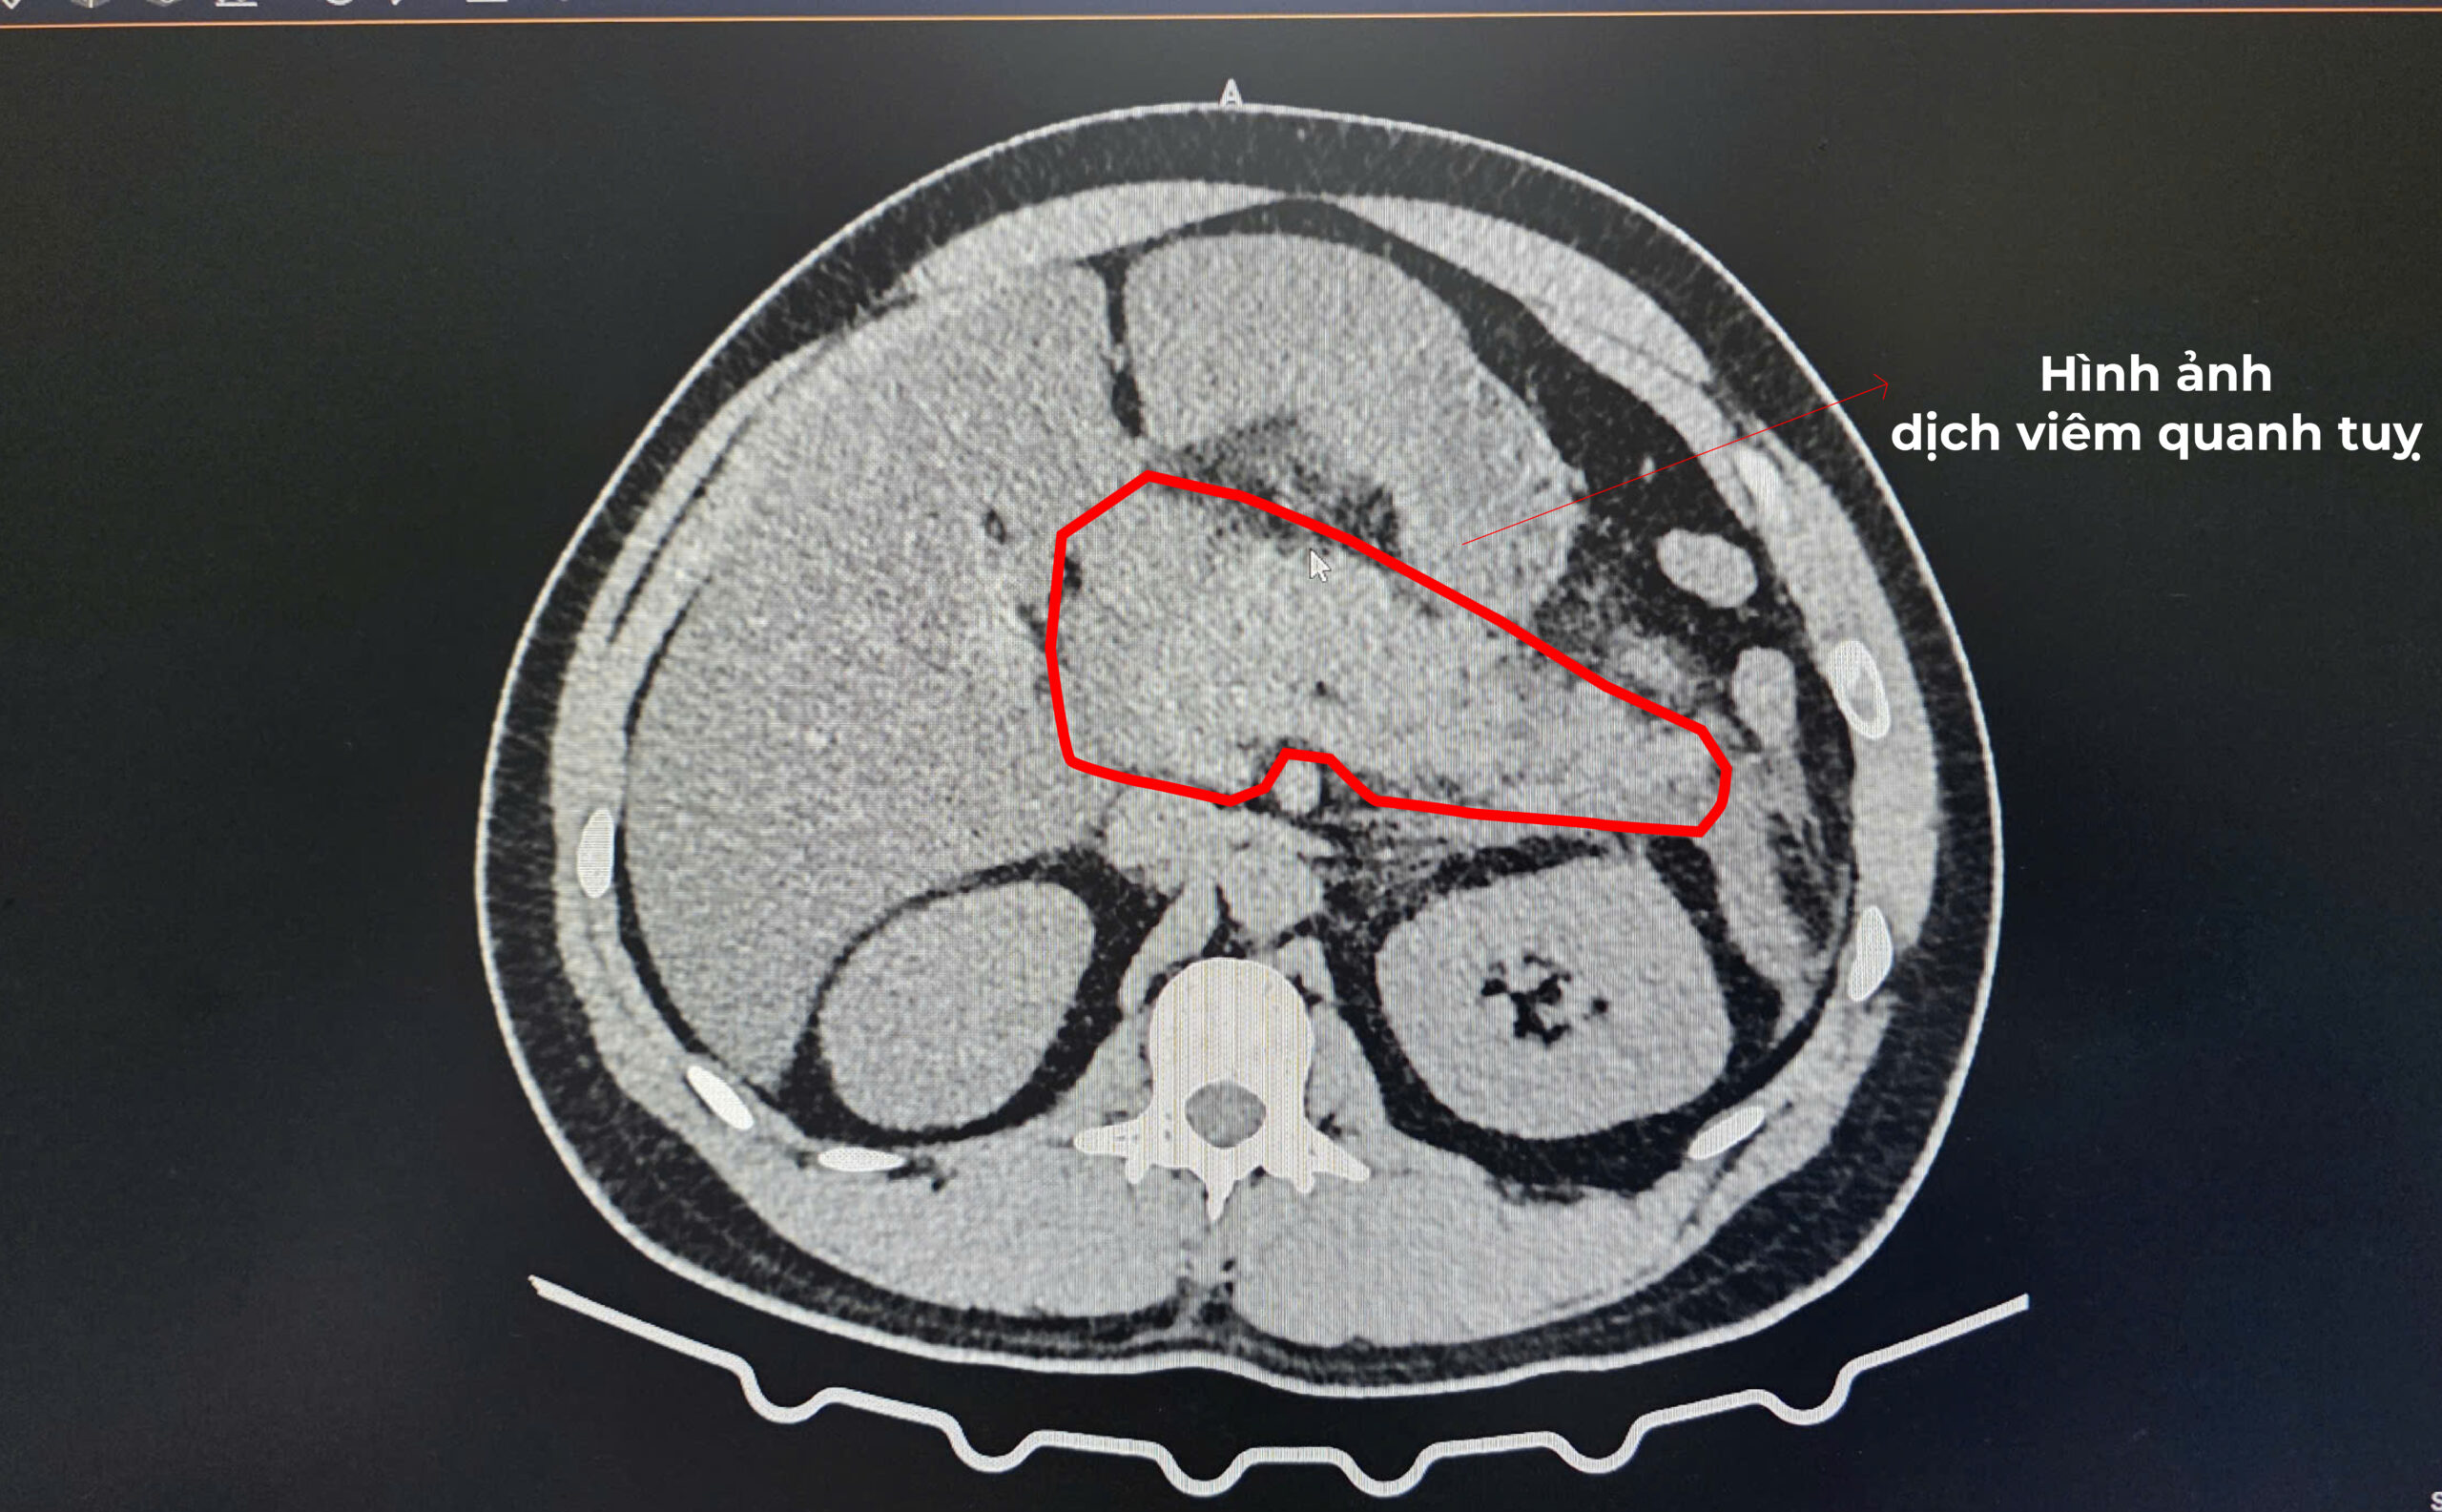

Hình ảnh chụp cắt lớp vi tính (CLVT) cùng các xét nghiệm cận lâm sàng đã xác định rõ tình trạng viêm tụy cấp nặng. Bệnh nhân được chẩn đoán viêm tụy cấp do tăng triglycerid máu và nhanh chóng được xử trí theo phác đồ chuyên môn: theo dõi sát toàn trạng, nhịn ăn giai đoạn đầu, nuôi dưỡng tĩnh mạch, đặt sonde dạ dày, bù dịch tích cực, sử dụng kháng sinh phối hợp liều cao, giảm đau, giảm tiết dịch vị dạ dày và kiểm soát chặt chẽ mỡ máu. Khi tình trạng lâm sàng cải thiện, bệnh nhân được chuyển dần sang chế độ ăn phù hợp theo đúng tình trạng bệnh.